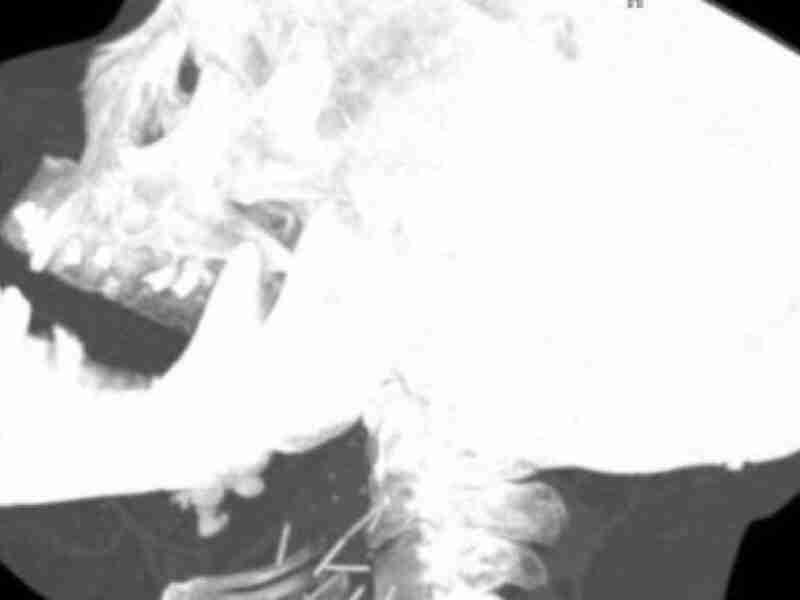

Ahora puedes leer el artículo de UpSocl sobre Adicto a la heroína va al hospital. Tras una radiografía, hallan lo más espeluznante en su cuello.

No hay que ser un genio para saber que las drogas son peligrosas. Y no solo por los efectos que estas pueden provocar o por su alto consumo que, fácilmente, puede llevar a una sobredosis y la muerte, sino también por los métodos que se emplean para consumirla. Y si hay una droga que se…